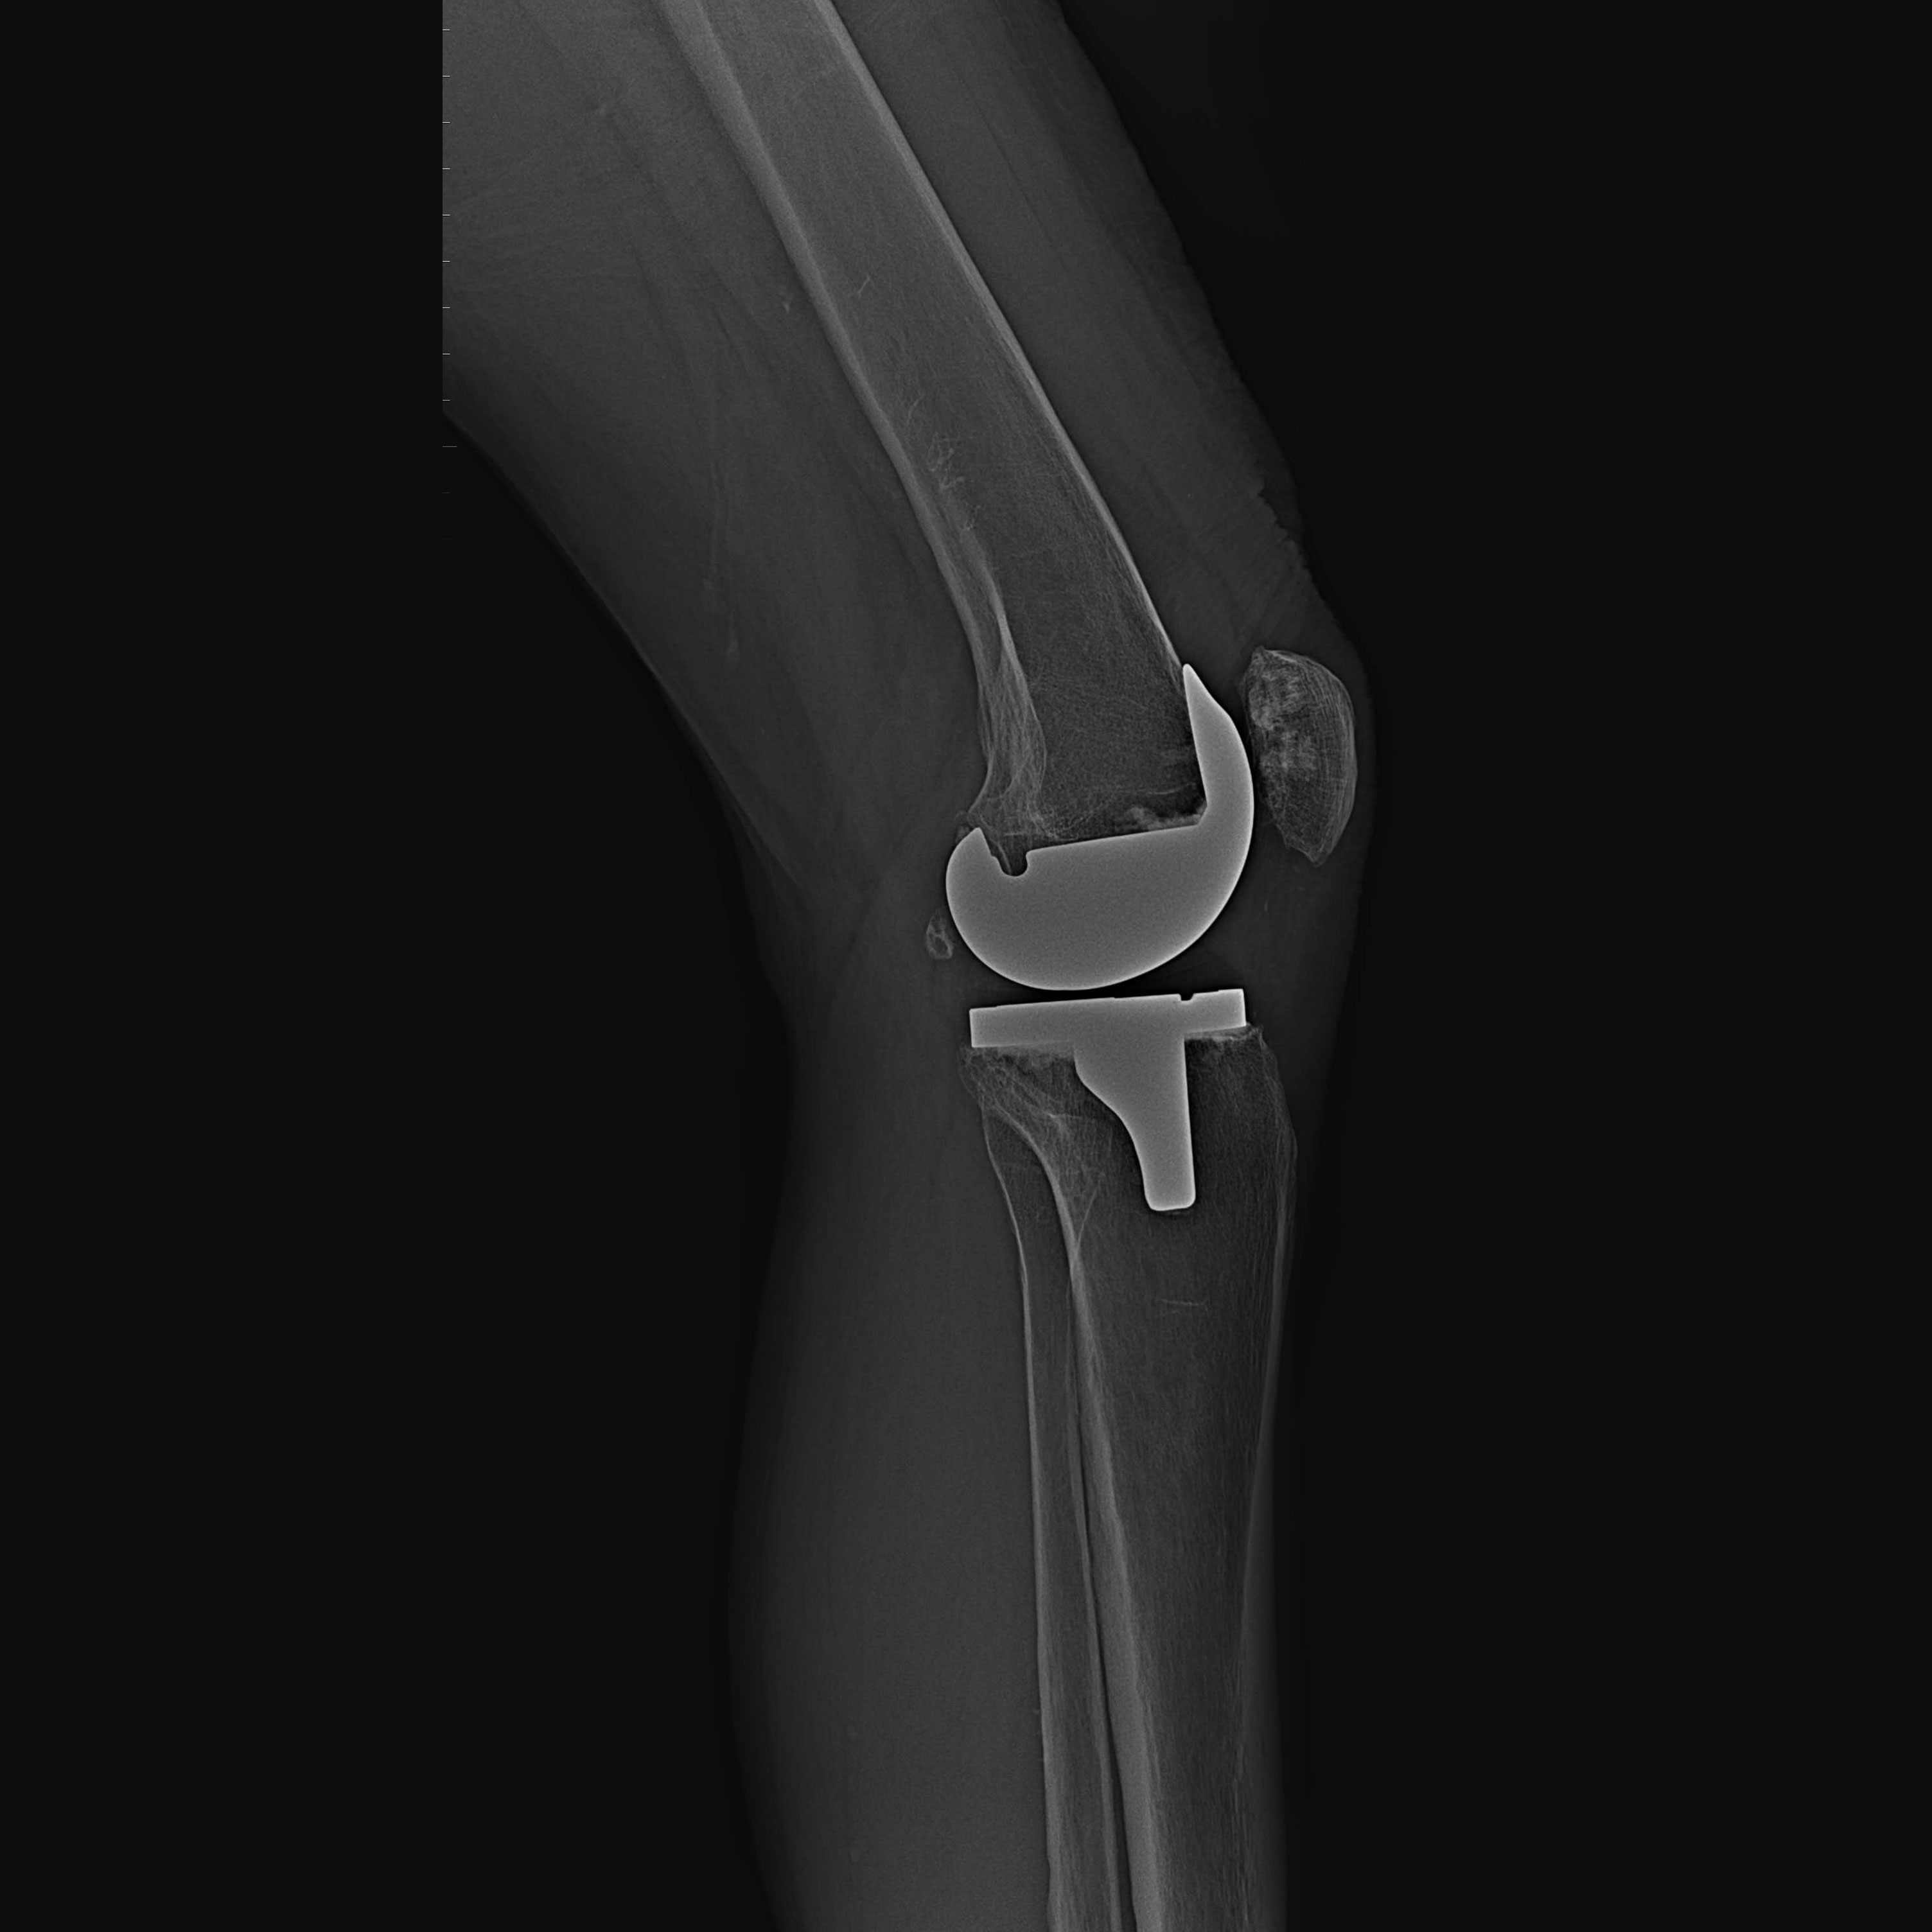

機器手臂手術 首頁 案例分享 膝關節手術 機器手臂手術 蔡女士 78歲 術前 術後 陳女士 70歲 術前 術後 術前 術後 ANGEVINE女士 73歲 術前 術後 U.S.A Mark 73歲 術前 術後 藍女士 78歲 術前 術後